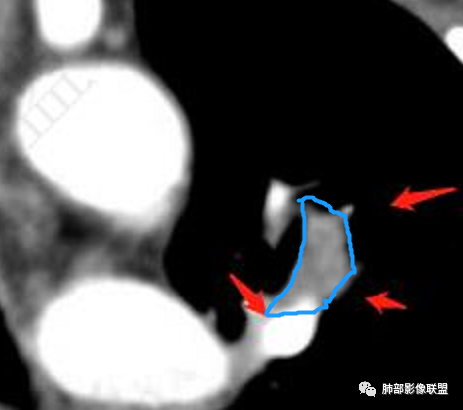

软组织+重建;病灶实性部分不是类圆形,密度相对均匀柔和。

肺门区病灶与支气管关系不密切,强化显著、磨玻璃晕等等容易想到的是肺腺癌。而不首先考虑与支气管密切相关恶性肿瘤,如鳞癌、类癌、粘液表皮样癌等等。

粘膜相关淋巴瘤(MALT)确实是符合的,但确实为我们遗忘!

1、连续3年观察,病灶逐步增大,符合惰性恶性肿瘤。2、支气管壁增厚,腔内内壁无变化——病灶长轴沿支气管周围蔓延;朝外走,内侧没有,提示病灶间质为主,与支气管无关。

支持淋巴瘤的关键点:1、间质为主;2、与支气管无关;3、边缘GGO的长期存在支持恶性

因为与支气管无关不支持腺癌,还是要警惕淋巴瘤。